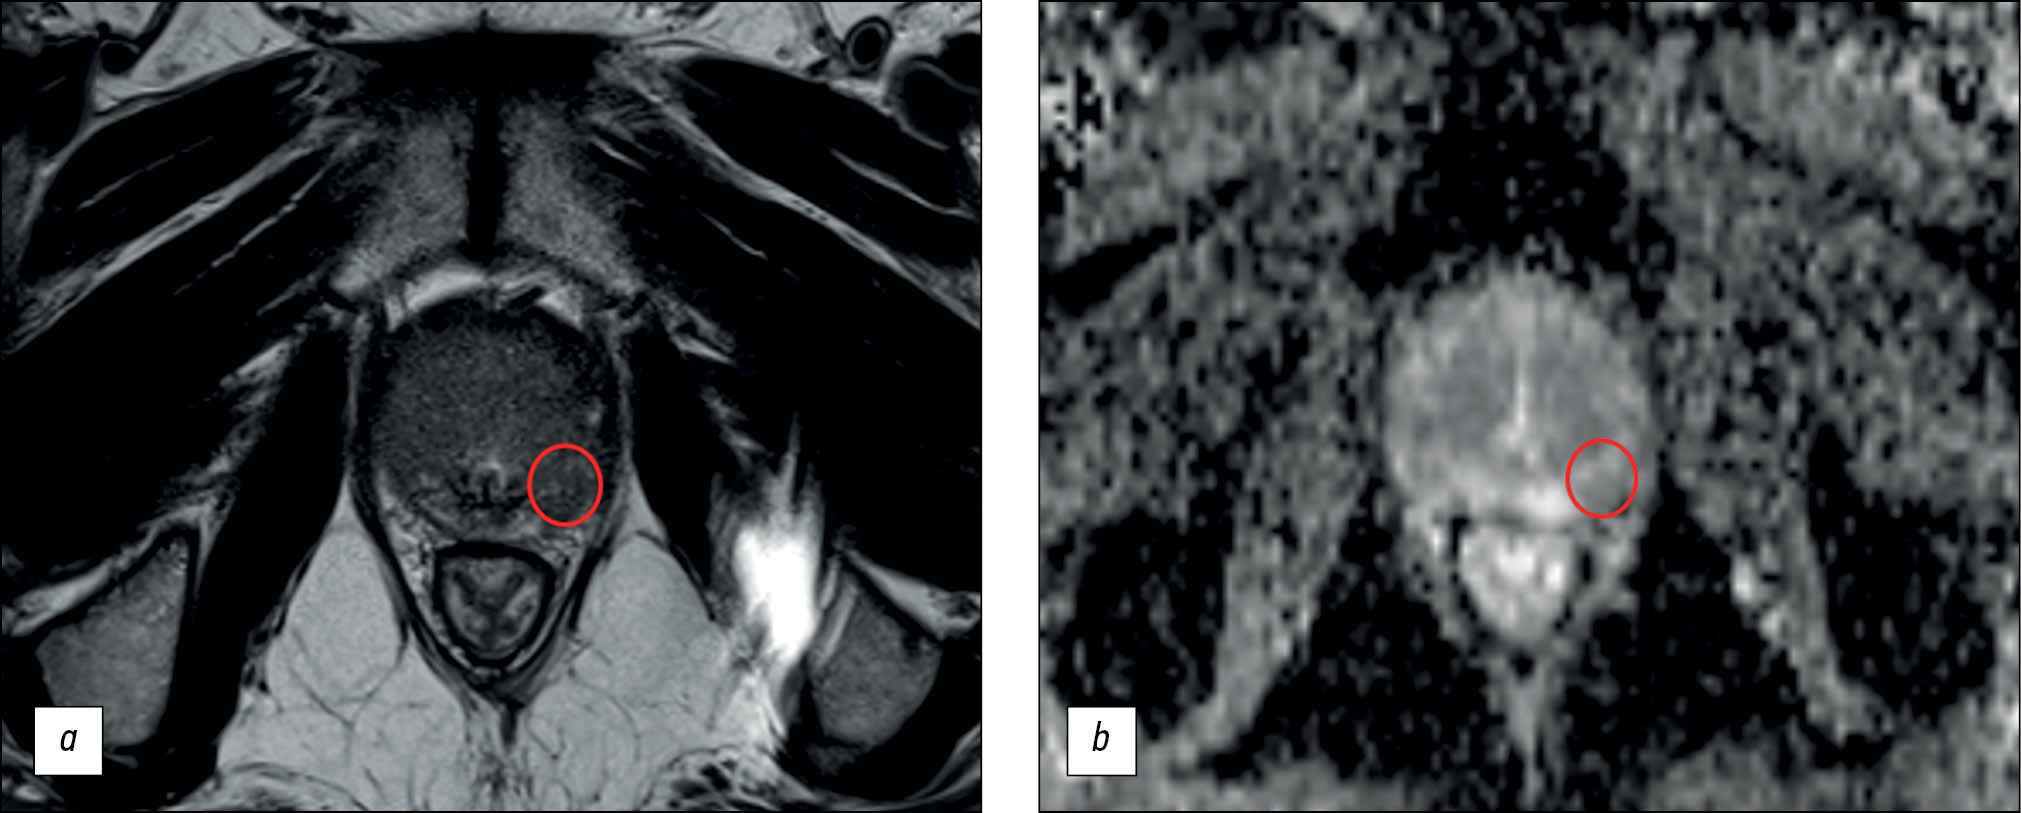

The main difference in mpMRI is the inclusion of DCE in the scanning protocol. This study demonstrates that DCE enhances the specificity of detecting prostate lesions by radiologists with <2 years and those with >5 years of experience (Tables 2 and 3; Fig. 2). However, radiologists with 2–5 years of background paradoxically experienced a decrease in specificity when evaluating the mpMRI datasets.

Fig. 2. An example of an increase in the PI-RADS category using dynamic contrast enhancement: a ― T2-weighted image in the axial plane: in the lateral posterior segment of the peripheral zone of the right lobe in the middle part of the prostate gland there is a focus of reduced signal corresponding to the zone of diffusion restriction; b - map of measured diffusion coefficient: this lesion was characterized by the physician as PI-RADS 3 using biMRI, but with dynamic contrast enhancement (c) the lesion shows early contrast enhancement, which allows it to be regarded as PI-RADS 4.

DCE imaging in prostate mpMRI has traditionally been limited by longer image acquisition times. This includes the time-consuming procedure of contrast administration, which involves preparing for the injection by catheterizing the patient. Longer analysis times for DCE images and higher software requirements are also important factors. However, DCE helped increase the diagnostic accuracy (66.4% vs. 61.7% for a radiologist with <2 years of experience and 70.1% vs. 68.2% for a radiologist with >5 years of experience).